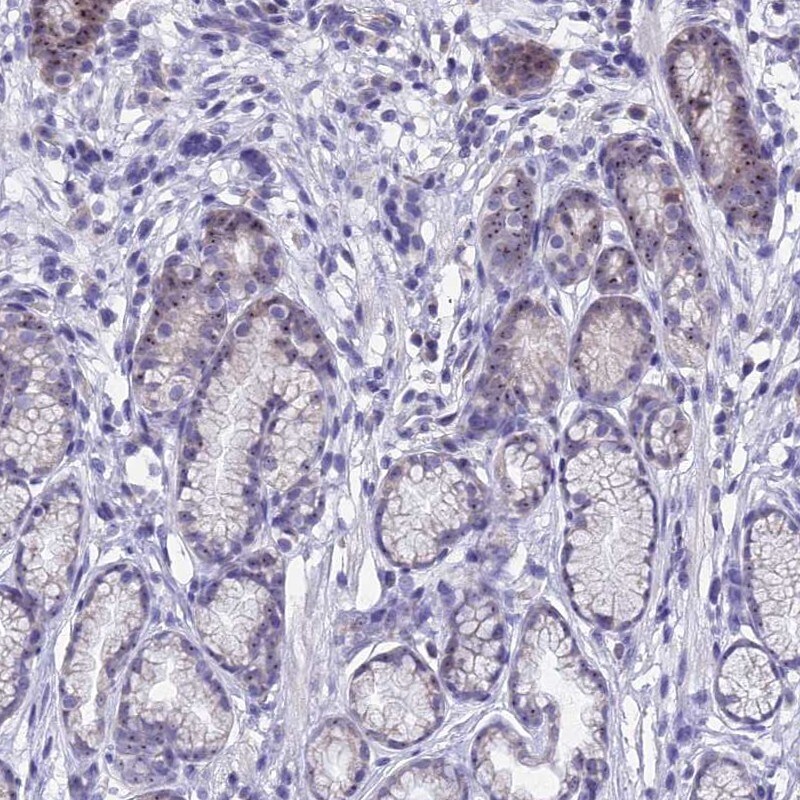

Supportive validation

- Submitted by

- Invitrogen Antibodies (provider)

- Main image

- Experimental details

- Immunohistochemical staining of KNOP1 in human stomach, upper using a KNOP1 Polyclonal Antibody (Product # PA5-59418) shows distinct nucleolar positivity in glandular cells.